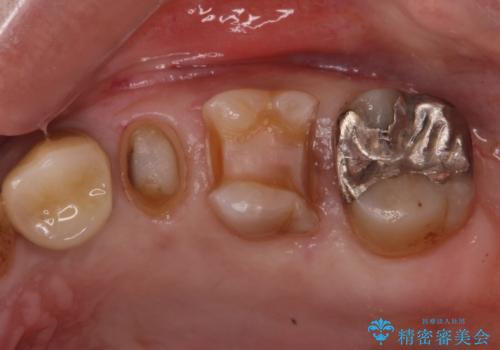

- 左上の歯が欠けたとの事で来院。

銀歯を除去し隣の歯も虫歯が見られたのでジルコニアクラウン、e-maxインレーで治療を行いました。

適合の良い被せ物、詰め物が入りました。